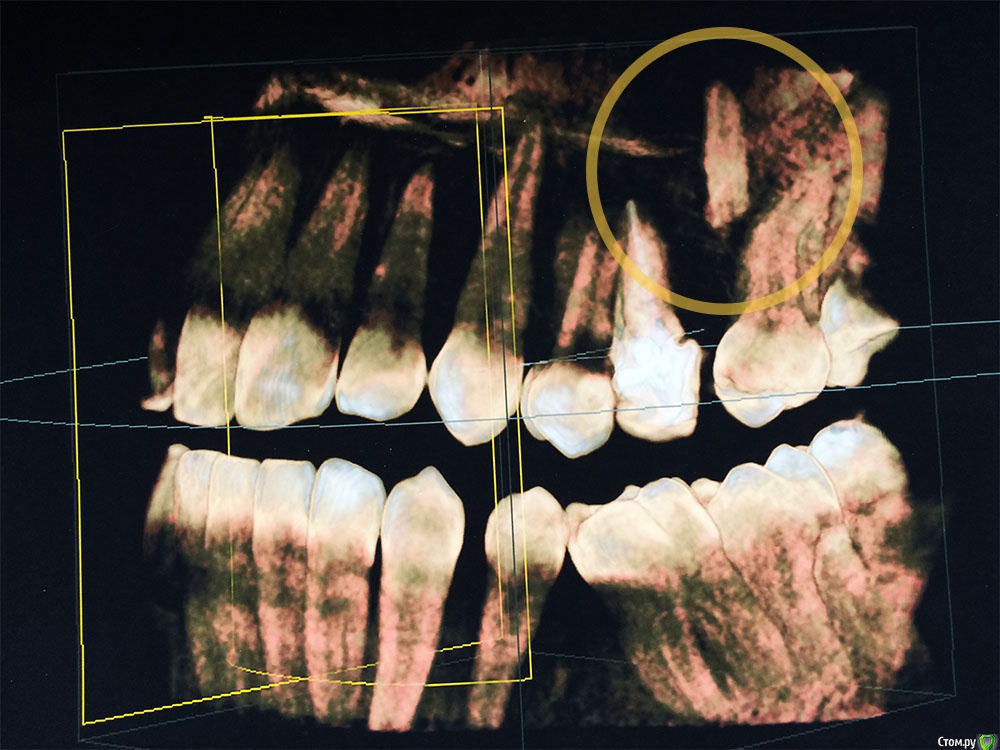

Подскажите, пожалуйста! Удалял зуб 10 лет назад, сейчас обнаружили на снимке, что он удален не полностью — остался кусок корня зуба, который очень глубоко затолкали при удалении, чуть ли не в пазуху носа.

Снимки прилагаю. Направили в ЧЛХ на операцию, собрал все анализы, противопоказаний нет, а ложиться не хочется, как обычно   :ph34r:

Здравствуйте, корень скорее всего не в пазухе, если имеете кт на руках, выставите срезы на корень, квадрат с перекрестьем на корень наведите и выложите срезы сюда, может ЧЛХ и не потребуется.